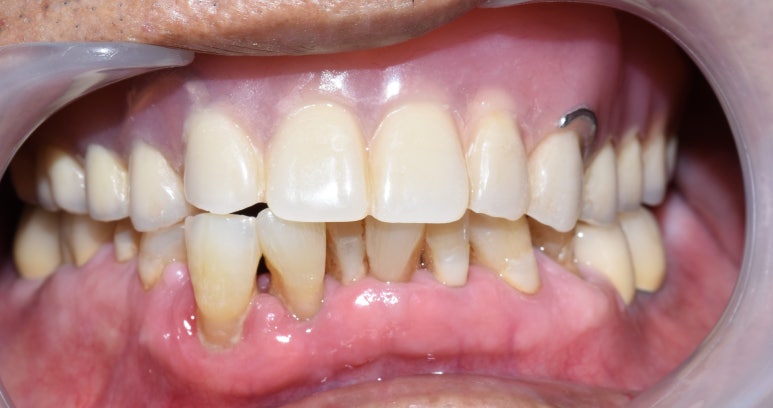

- 오래된 상악틀니 → 2. 틀니제거시 모습 → 3.상악전체 임플란트

- 오래된 틀니를 새 전체틀니로, 아래앞니 부위는 임플란트

오래된 상악틀니를 상악 전체 틀니로 교체

아래 앞니부위 임플란트까지 한 후